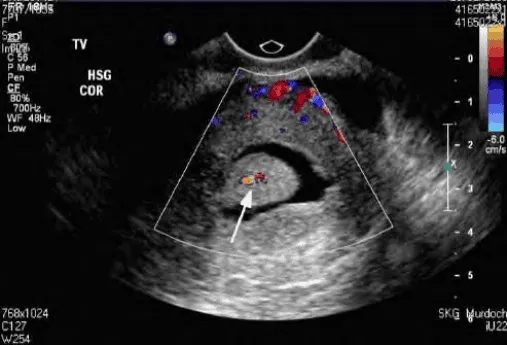

Siêu âm bơm nước (SIS) nếu nghi polyp hoặc dính buồng tử cung: Bơm nước làm nổi bật khối, giúp xác định vị trí và kích thước tổn thương.

Hình ảnh “Siêu âm bơm nước buồng tử cung (SIS): Phát hiện polyp lòng tử cung. Khi có tổn thương khu trú như này, không thể chẩn đoán xuất huyết cơ năng”.

Hình ảnh siêu âm phụ thuộc vào pha chu kỳ. Thực hiện sau sạch kinh giúp tránh nhầm tăng sinh nội mạc giả do nội mạc phát triển dưới estrogen giai đoạn giữa chu kỳ.